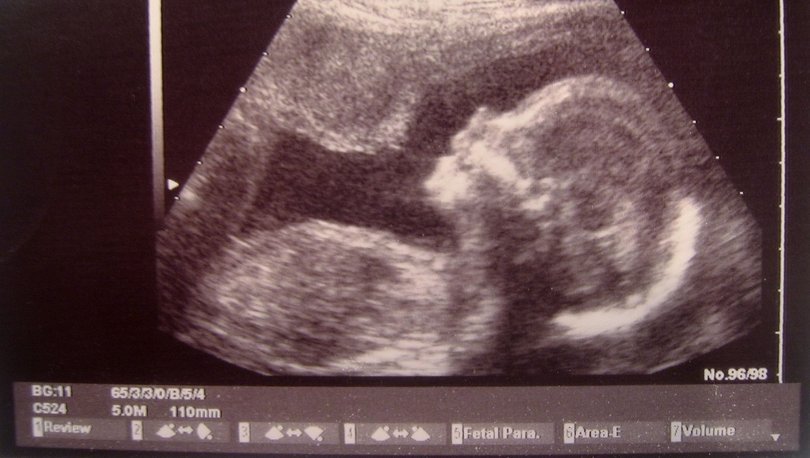

İki Taraflı Zahmetsiz Tüp Bebek (ER-IVF) adı verilen deneysel yöntemle her ikisi de döllenme sonrası oğullarını fiziksel olarak bedenlerinde taşıdı.

Bir donörden sperm alındı. Bliss'in döllenen yumurtası, kuluçka makinesi yerine Bliss'in rahminde ilk oluşum sürecini tamamladı. Beş gün sonra da bebek hormon terapisi alan Ashleigh'e nakledildi.